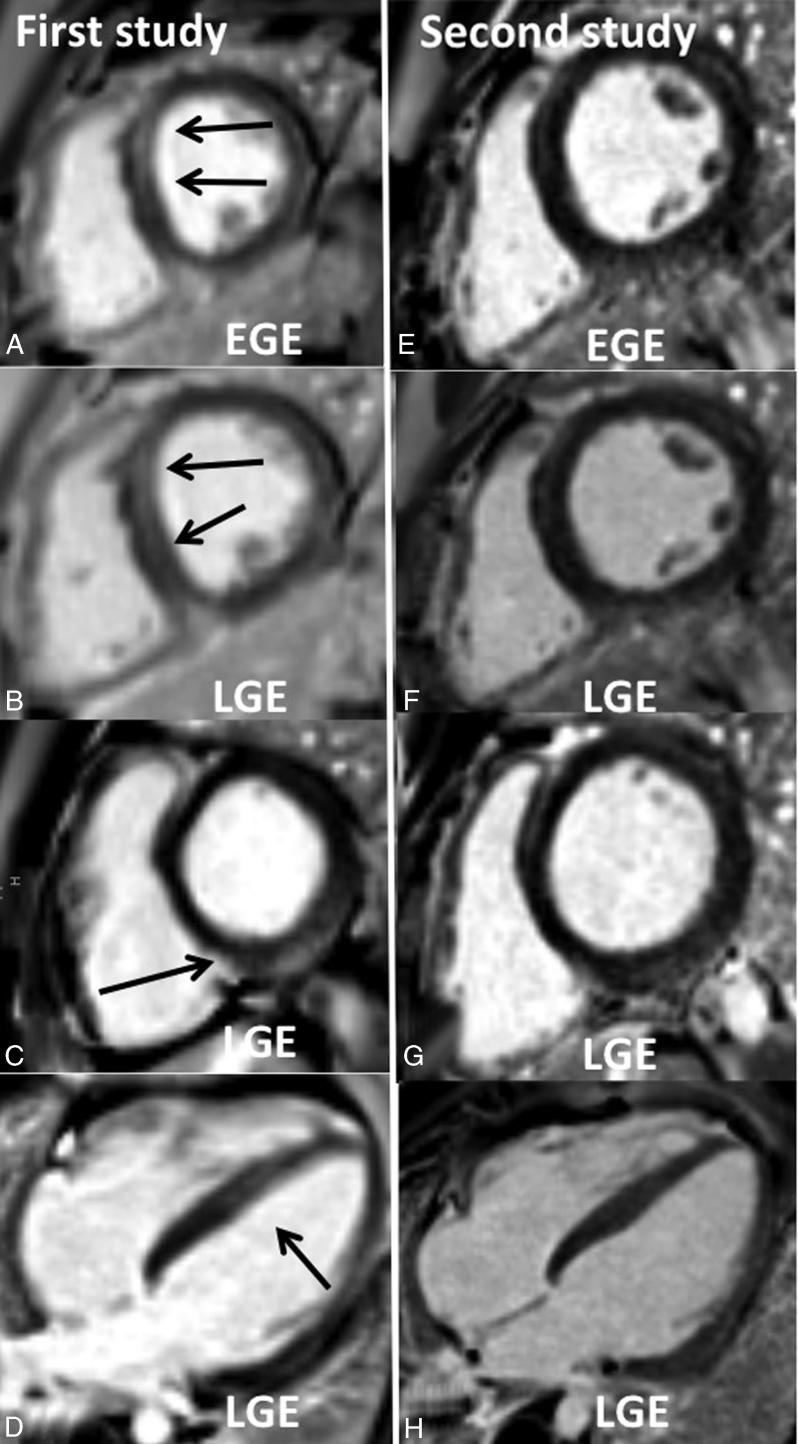

Cunningham Michael E A, Doroshow Robin, Olivieri Laura, Moak Jeffrey P

Division of Cardiology, Children's National Health System, Washington, DC.

HeartRhythm Case Rep. 2016 Nov 29;3(2):124-128. doi: 10.1016/j.hrcr.2016.09.015. eCollection 2017 Feb.